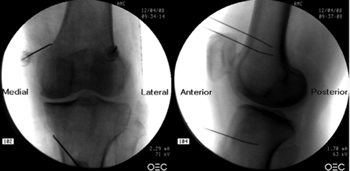

To perform a fluoroscopic-guided TRFGN, we need an anteroposterior (AP) and lateral view of the knee (Figure 2). First we place the patient in supine position with a pillow under the popliteal fossa (to make the patient more comfortable) (16). After performing asepsis and antisepsis of the knee, we proceed to locate the GN (Table II). SLGN is advancing the TFR needle toward the confluence of the lateral femoral diaphysis with the lateral femoral condyle in an AP view and at a mid-point of the femur in a lateral view. The SMGN is located by advancing the needle toward the confluence of the medial femoral diaphysis with the medial femoral condyle in an AP view and at a mid-point of the femur in a lateral view. Finally, the IMGN is located by advancing the needle toward the confluence of the medial tibial diaphysis with the tibial epicondyle in an AP view and at a midpoint of the tibia in a lateral view (16,17).

Fig. 2. Anteroposterior (AP) and lateral projection where therapeutic targets are observed using fluoroscopy. Image taken from Choi et al. (9). Reproduced with the permission of Jin Woo Shin.

Good AP and lateral view is very important. In AP projection, the tibiofemoral joint should have a similar width on both sides of the knee with the interspace open (9). In lateral projection, there must be a correct overlap of both femoral condyles to perform a satisfactory blockage of the SMGN and SLGN (18).